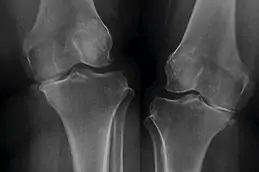

يُعد علاج البلازما الغنية بالصفائح الدموية للركبة، المعروف أيضًا بحقن البلازما للمفاصل، من الأساليب الرائدة في مجال الطب التجديدي، ويُستخدم هذا العلاج بشكل فعّال في حالات آلام الركبة وتلف المفاصل، حيث يعتمد على استخلاص مكونات البلازما من دم المريض نفسه، ثم إعادة حقنها في المنطقة المصابة، يهدف هذا الإجراء إلى تحفيز عملية الشفاء الطبيعي في الجسم، وتسريع تجدد الأنسجة، مع تقليل الالتهاب وتخفيف الألم بشكل ملحوظ.

تُعد حقن البلازما الغنية بالصفائح الدموية (PRP) أحد الأساليب المستخدمة في علاج الركبة، حيث يُؤخذ مقدار صغير من دم المريض ويُعالج باستخدام جهاز الطرد المركزي لفصل مكونات الدم، واستخلاص البلازما والصفائح الدموية، بعد ذلك يُعاد حقن هذا التركيز مباشرة في الركبة أو المفصل المتضرر للمساعدة في تعزيز الشفاء.

| خشونة المفاصل (الفُصال العظمي): | يمكن لعلاج PRP أن يخفف الألم ويحسن وظيفة المفصل لدى مرضى خشونة الركبة عن طريق تحفيز تجديد الأنسجة وتقليل الالتهاب. |

بعد مرور شهرين إلى ثلاثة أشهر من العلاج بـ PRP، يحدث انخفاض كبير في ألم الركبة والتورم والتصلب، ووفقًا لاستبيان حديث، أفاد المرضى الذين خضعوا لعدد 2-3 جلسات من حقن PRP للركبة بتحقيق نتائج ممتازة دون حدوث مضاعفات، على الرغم من أن علاج PRP يعتبر فعالًا في تخفيف ألم الركبة، إلا أن نتائجه ليست دائمة تمامًا، ويوصى بإجراء جلسات متابعة سنوية للحفاظ على فعالية العلاج لفترة أطول.